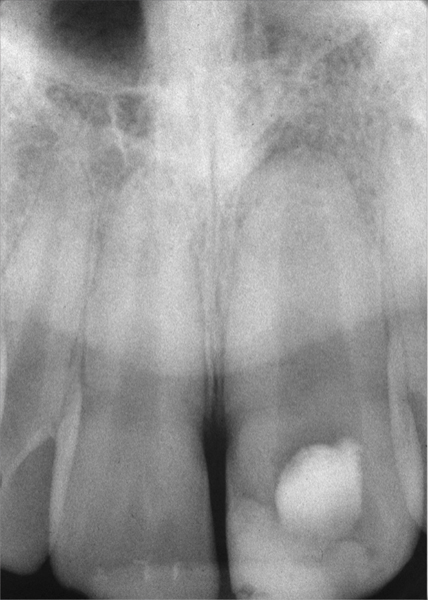

Clinical procedure: Regeneration of the endodontic pulp space is indicated for cases with very thin dentinal walls and an open apex that is more than 1 mm in diameter radiographically (Figure 4). Disinfection of the root canal system is performed using sodium hypochlorite irrigation followed by a triple antibiotic paste dressing that is left in place for 1 week. At the second visit, ethylenediaminetetraacetic acid (EDTA) is used to condition the dentin walls, which results in the release of growth factors, and bleeding is stimulated in the periapical tissues (where stem cells are located), with the aim of filling the pulp space with a stable blood clot, which would serve as the scaffold. MTA is then placed at the canal orifice in contact with the clot to protect it from coronal microleakage (Figure 5 and Figure 6). In time, the clot should be replaced with a reparative tissue of variable composition, and the root walls should continue to thicken due to the deposition of a dentin-like material on the pre-existing root dentin27,28 (Figure 7 and Figure 8).

Fig 4. Preoperative radiograph showing aggressive external root resorption and thin dentinal walls.

Figure 4

Fig 5. Working length confirmation.

Figure 5